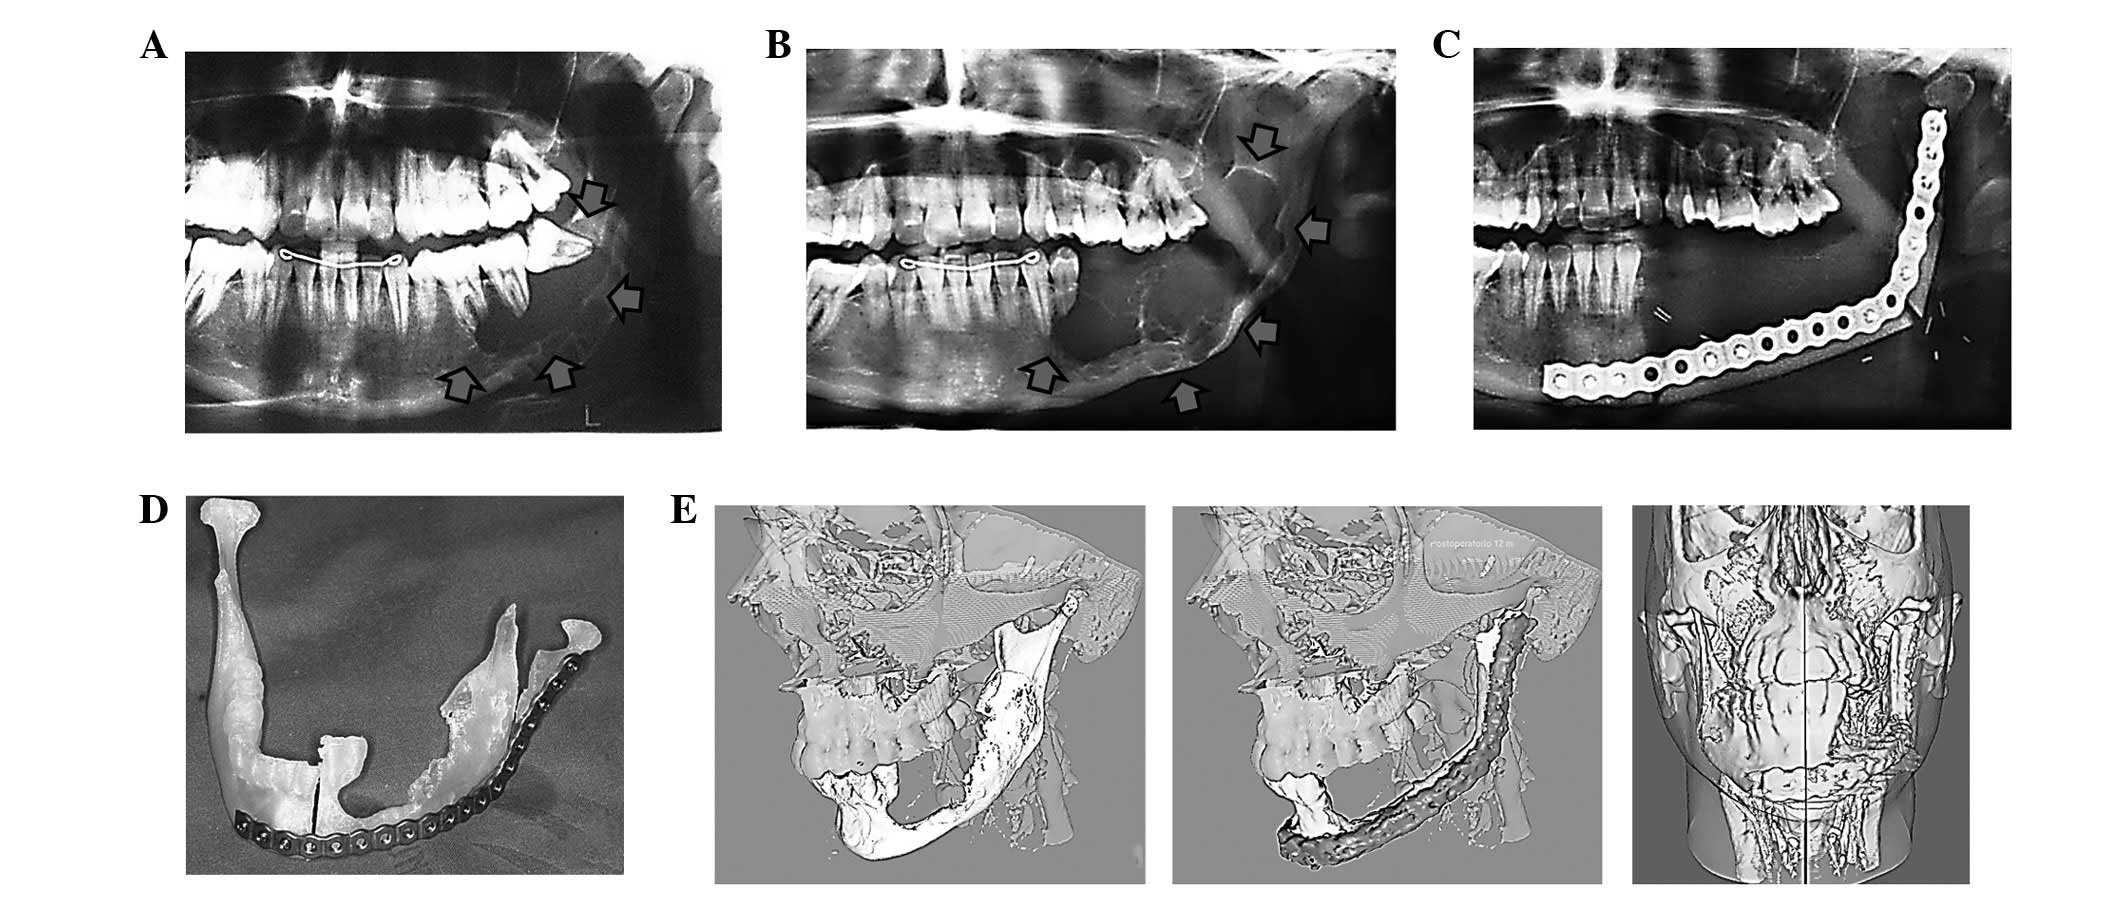

Ниже представлены несколько фотографий, иллюстрирующих различные формы рака слизистой. Ознакомьтесь с ними, чтобы лучше понять внешние признаки этого заболевания: